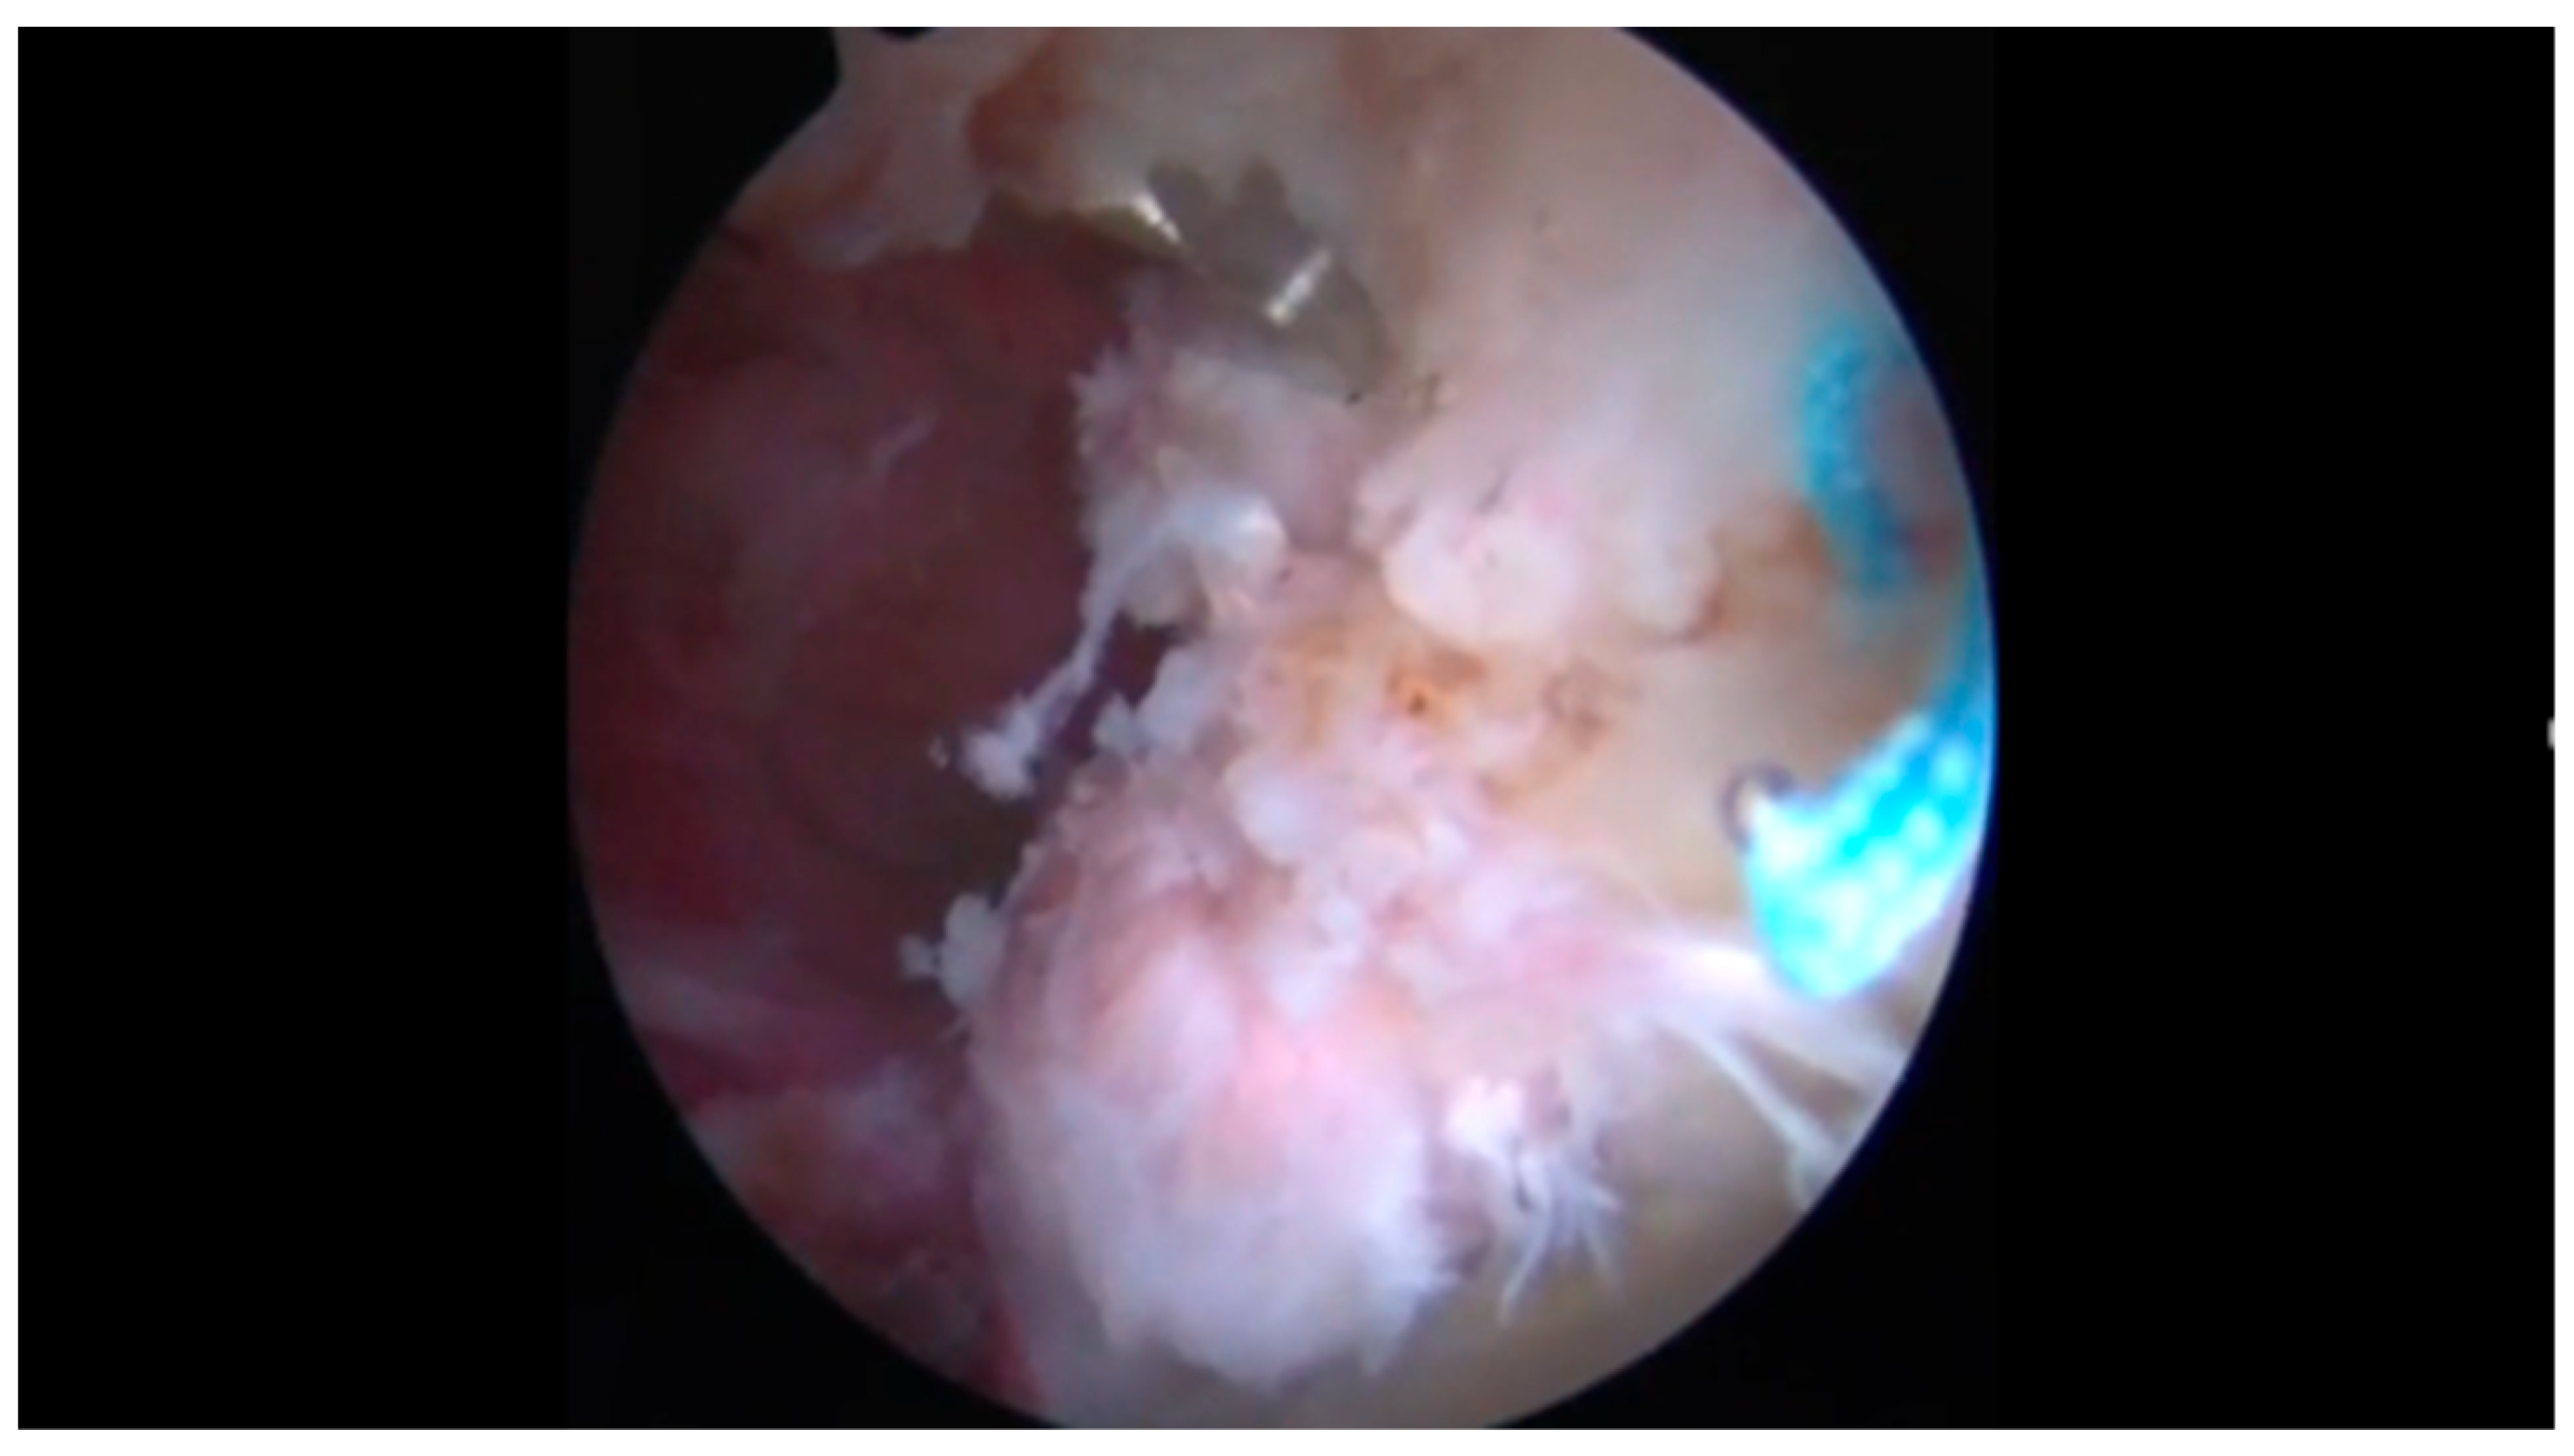

2.2. Surgical Procedure